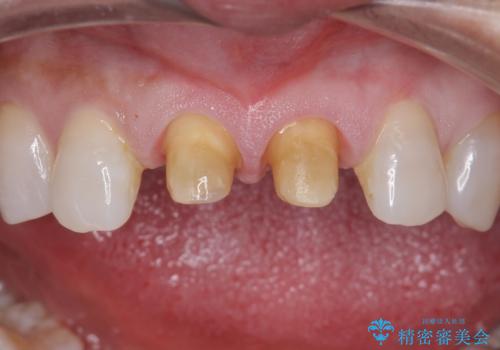

- 前歯につけていたべニアが取れたとのことで来院された患者様です。

より脱離リスクの低いクラウンでの修復を行います。

- 右上1左上1 : 仮歯/11,000円×2、ジルコニアクラウン(スペシャル)/154,000円×2 合計330,000円(税込)費用は治療当時の料金となります

取れていない方のべニアも周囲の歯と色調が合っていなかったため、一緒にやり替えました。